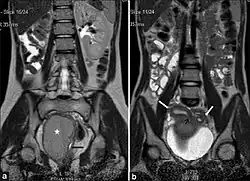

(a) Coronal Single shot T2W image shows absence of the right kidney. The distended hemivagina (asterisk) is seen on the right side and the normal collapsed left hemivagina with minimal fluid is seen adjacent to it (black arrow). The distended hemivagina ends above the introitus and its contents are hypointense to fat. (b) Coronal Single shot T2W image shows right and left uterine horns (white arrows). The right uterine horn cavity is seen to communicate with the upper end of the fluid collection in right hemivagina (small black arrow).